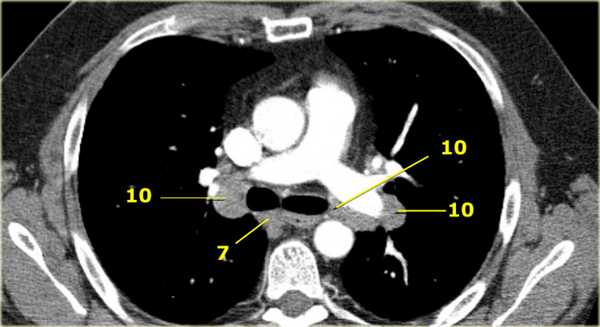

На изображении слева 3А узел в преваскулярном пространстве. Обратите внимание так же на ниже расположенные паратрахеальные узлы справа относящиеся к 4R группе.

4L. Левые нижние паратрахеальные лимфатические узлы

4L узлы расположенные слева от левой стенки трахеи, между горизонтальными линиями проведенными касательно верхней стенке дуги аорты и линией проходящей через левый главный бронх на уровне верхнего края верхнедолевого бронха. Они включают паратрахеальные узлы расположенные кнутри от артериальной связки.

Узлы 5 группы (аортопульмонального окна) расположены кнаружи от артериальной связки.

На левом изображении над уровнем легочного ствола представлены нижние паратрахеальные узлы слева и справа, так же здесь представлены узлы 3 и 5 групп.

Изображение слева выше уровня карины. Слева от трахеи 4L узлы. Обратите внимание что они расположены между легочным стволом и аортой, но не в аортопульмональном окне, потому что они лежат медиальнее артериальной связки. Лимфатические узлы латеральнее легочного ствола относятся к 5 группе.

10. лимфатические узлы корня легкого

Лимфатические узлы корня расположены проксимальнее долевых узлов, но дистальнее медиастинальной дупликатуры и узлов промежуточного бронха справа.

Все лимфатические узлы 10-14 групп являются N1 узлами, так как они находятся вне средостения.